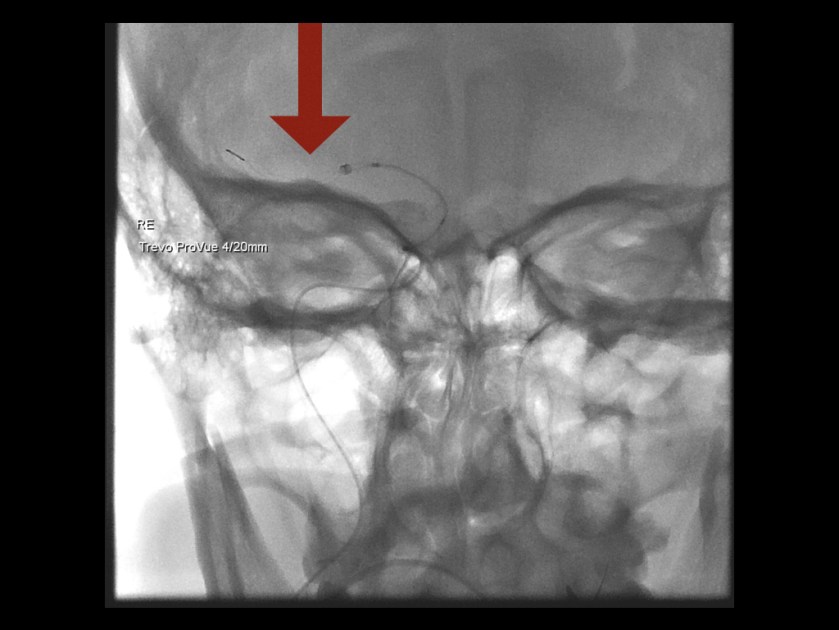

DSA (digitale Subtraktionsangiografie):

Aufsuchen des Gefäßverschlusses und Durchstoßen des verstopfenden Thrombus mittels Draht (Pfeil). Anschließend wird der Thrombus mittels eines eigenen maschenartigen „Retrievers“ aus dem Gefäß gezogen.